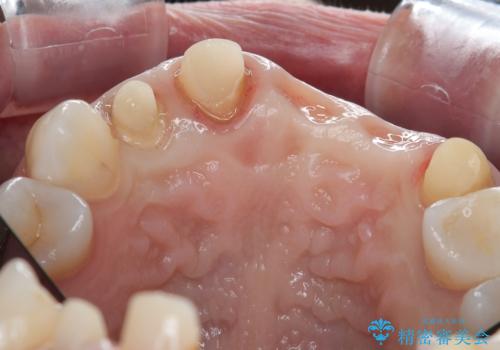

- 前歯がグラグラし、においもする、とのことで改善を求めて来院されました。

一見して問題ないように見える左側の2前歯は、セラミックを除去してみると亀裂や虫歯の再発が見られました。

抜歯時に可及的に歯肉のボリュームを保つよう骨充填材とコラーゲン製剤による填塞を行い審美的かつ機能的なブリッジとなるよう治療を進めます。